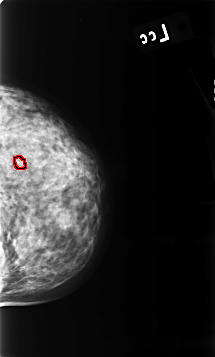

B_3455_1.LEFT_CC

FILE: B_3455_1.LEFT_CC.OVERLAY

TOTAL_ABNORMALITIES 1

ABNORMALITY 1

LESION_TYPE CALCIFICATION TYPE COARSE DISTRIBUTION N/A

ASSESSMENT 2

SUBTLETY 5

PATHOLOGY BENIGN_WITHOUT_CALLBACK

TOTAL_OUTLINES 1

BOUNDARY